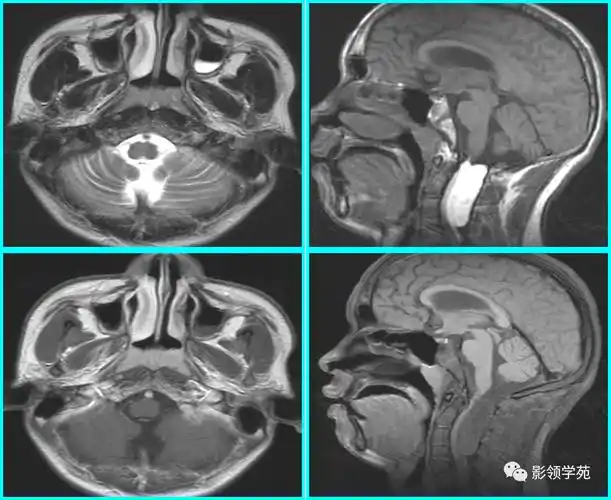

儿童腺样体肥大影像表现及诊断标准

x线高清图谱儿童腺样体肥大影像表现及诊断标准